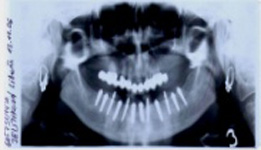

Bezzubá čelist je hlavní indikací pro ošetření pomocí implantátů. Zejména celkové zubní náhrady v dolní čelisti mají velice nízkou stabilitu a držení díky velkému úbytku kosti.

S pomocí zubních implantátů můžeme díky různým kotevním systémům (třmeny, kulové hlavy, Locatory) zajistit stabilitu a držení protézy nebo při použití většího počtu implantátů zhotovit pevné náhrady – můstky nalepené nebo našroubované na pevno na implantáty.

S těmito typy náhrad můžeme dosáhnout perfektní funkci, výbornou estetiku, fonetiku a současně zajistit u pacienta možnost dobré hygienickou péče a čištění, která je pro životnost implantátů velice důležitá.